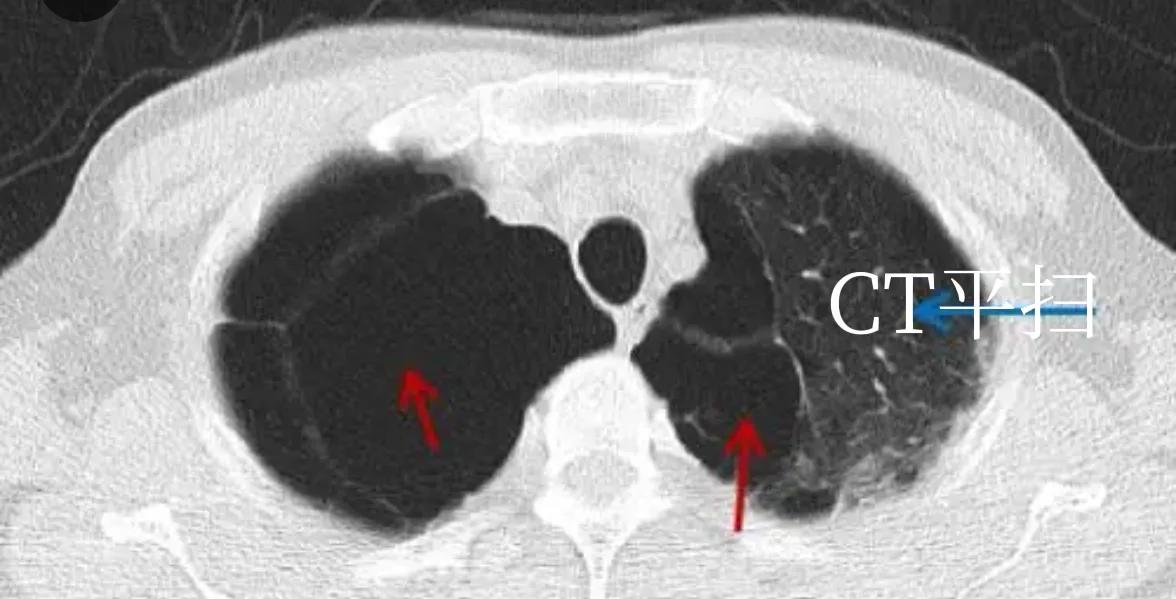

肺大泡常见于青年(先天性发育异常)和老年人(继发性肺部病变)中, 少年因气胸发作时 CT 发现肺大泡。老年人(吸烟者 主)及部分粉尘从业人员因体检发现。肺大泡严重者大多有呼吸困难等症状。胸腔镜微创手术,是最佳选择。薄层 CT 能够很好区别肺大泡和气胸。#创作#